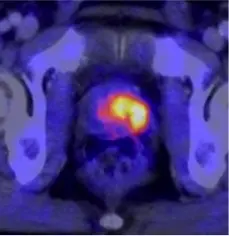

Next door, at DKFZ, scientists are laying the groundwork for future achievements in cancer diagnostics and treatment. DKFZ sets benchmarks, particularly in the field of modern magnetic resonance imaging (MRI). Just recently, a highly innovative PET-MR device combining MRI with positron emission tomography (PET) has started operating. Professor Heinz-Peter Schlemmer, head of the Radiology Division, explains: “This enables us not only to image high-resolution structures down to millimeter range, but also to obtain biological information from the images. This is particularly relevant in prostate cancer diagnosis." Prostate cancer often shows great differences in malignancy, and not every cancer requires surgery or radiotherapy. So far, however, clinicians often do not know which cases require immediate intervention and which cases justify watchful waiting because the cancer is growing slowly. “Advanced imaging methods contribute substantially to making an exact diagnosis at an early stage and to choosing an individually tailored treatment for the patient," says Schlemmer.